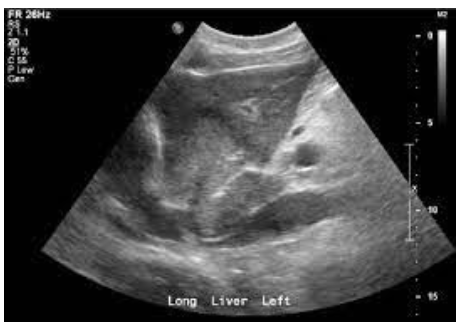

What pathology is found below?

Distal cholongiocarcinoma

Focal irregular ductal construction, wall thickening